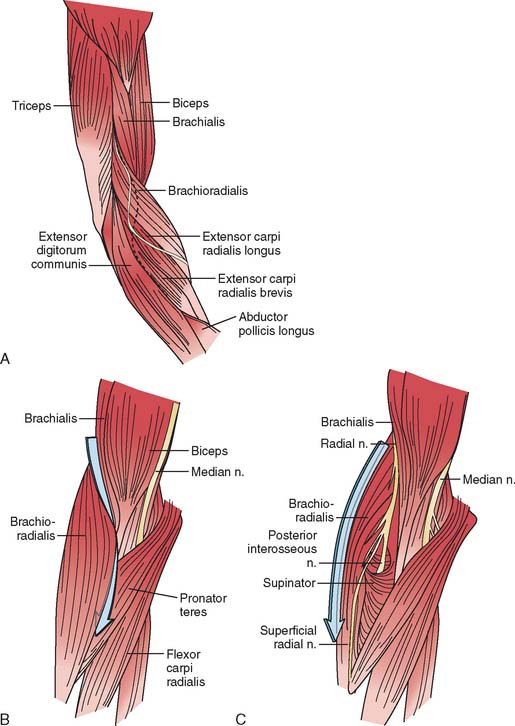

Анатомия и функции мышцы brachioradialis